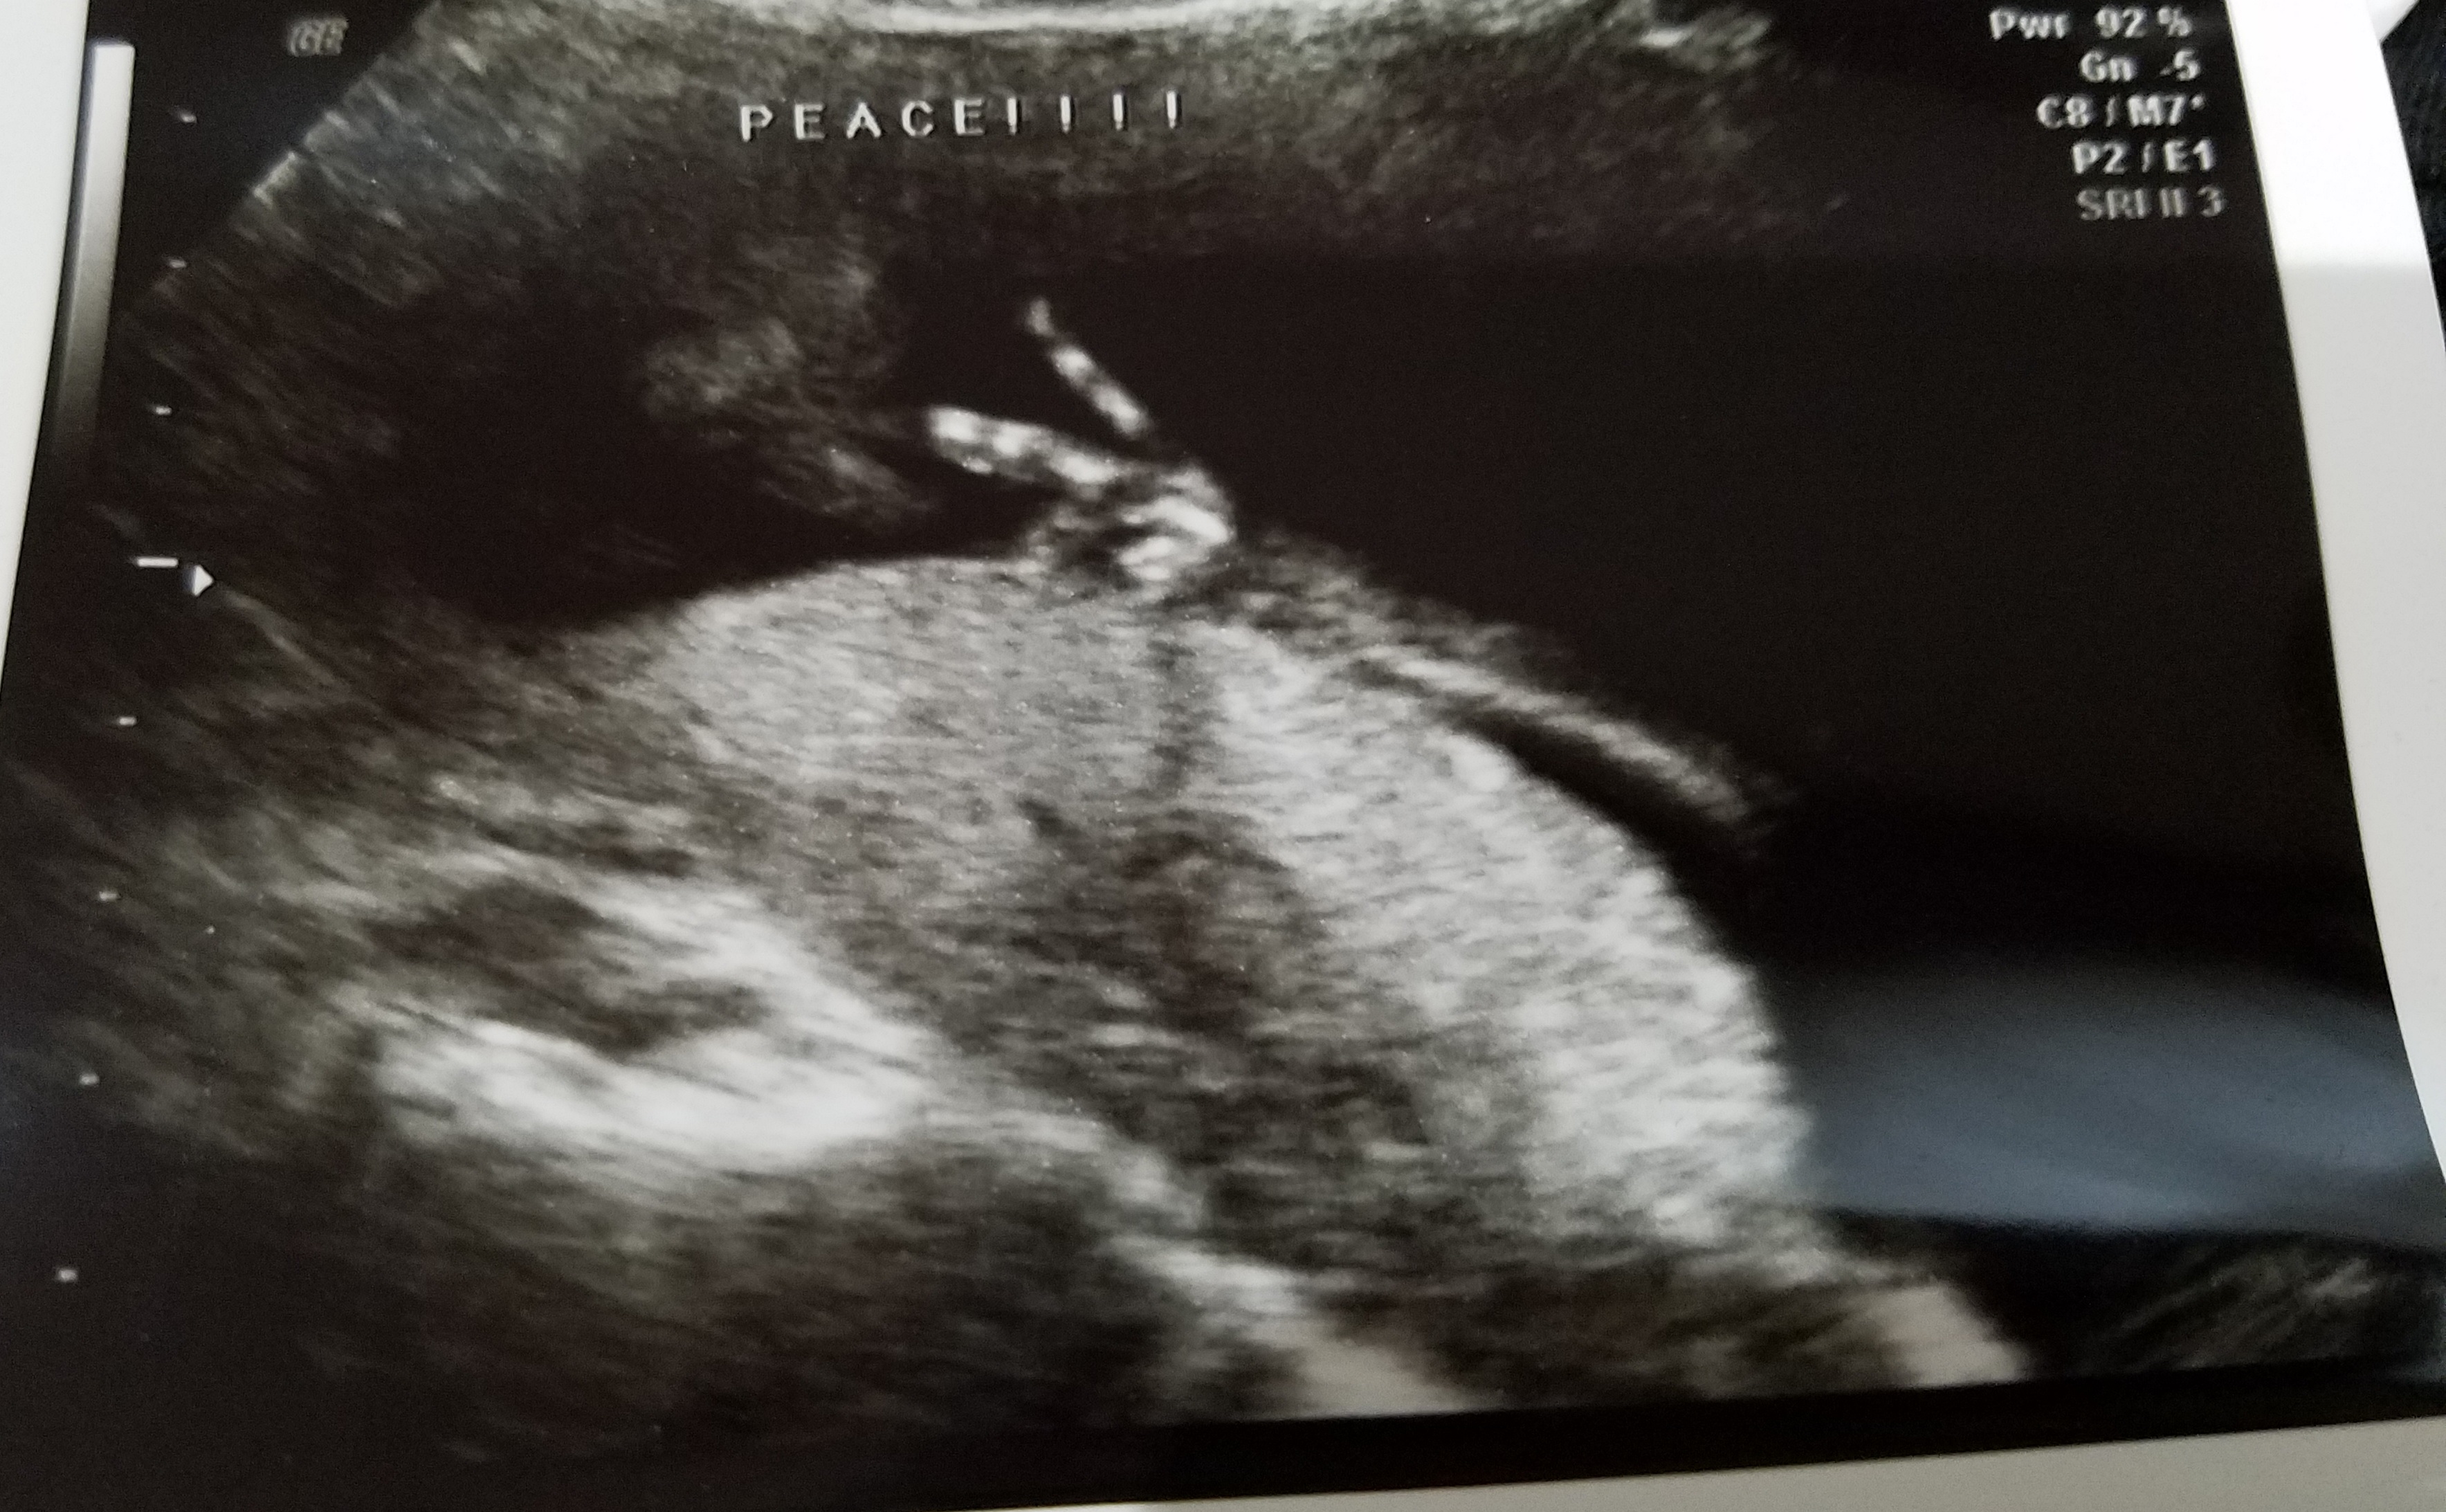

peace 18wks Published August 25, 2017 at 3535 × 2185 in Lucky Bean In Utero « Previous Next » 18 Weeks Like Loading...